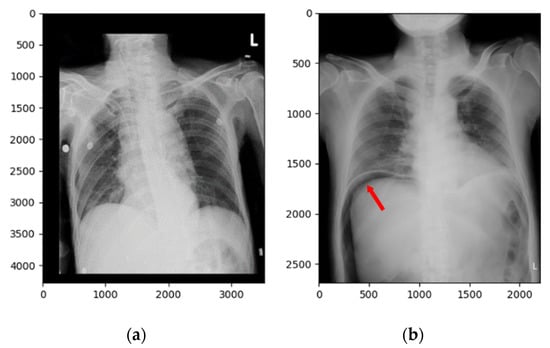

For technical diligence, evidence in the literature showed that the trained convolutional neural network fed with chest radiographs can actually meet the desired level of performance, and the amount of chest radiographs obtainable in the project made it feasible [18]. In addition, sufficient data for our study were obtained from the clinical radiology archive at Kaohsiung Medical University Hospital, a 1600-bed medical center in Taiwan, following approval granted by the Institutional Review Board (KMUHIRB-E-(II)-20190289). A total of 667 frontal chest X-ray images with and without subphrenic free air taken at the ED (annual census of around 96,000 patients per year) between 2007 and 2018 were included in the study. Initial pneumoperitoneum labels were obtained by combining the surgical operation records and findings from the radiology report archive. We collected one frontal chest X-ray image from each case with a total of 667 images. These were randomly divided into a training set (587 images) and a testing set (80 images) for model construction, with the ratio of positive and negative cases shown in Table 1. There was no overlapping of images between sets. The training set included only images referred from the ED, where lateral films and cross-sectional CT imaging are not routinely available in the first place and clinical decision-making is usually mandated prior to a formal radiology report. The prevalence of hollow organ perforation among the patients in the test set was 50%, whilst that among patients in the training set was lower (38.67%). Figure 2 shows two frontal chest X-ray image examples. One is from a normal image and the other is a pneumoperitoneum image.

Figure 2. Frontal chest X-ray images of (a) a negative (normal) case and (b) a positive (pneumoperitoneum) case. The red arrow shows subphrenic free air, indicating pneumoperitoneum.